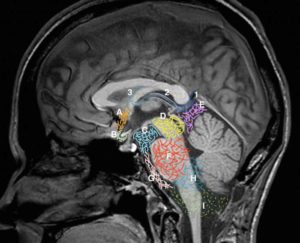

В местах, где субарахноидальное пространство естественным образом расширено, образуются мозговые цистерны, это значит, что основной объем циркулирующей цереброспинальной жидкости содержится в этих полостях. Подпаутинные цистерны – зоны естественного увеличения объема субарахноидального пространства, которые преимущественно находятся у основания мозга головы. Самые большие цистерны – базальная и затылочная.

Размеры субарахноидального пространства в норме в 3 месяца не превышают 3 мм у доношенных младенцев, 4 мм – у недоношенных детей. Нормальные размеры мозговых цистерн составляют: большая цистерна, расположенная под мозжечком – до 10 мм (сагиттальный срез), цистерна четверохолмия – до 3 мм. Объем циркулирующего ликвора составляет около 120-140 мл.

Если в ходе исследования в формате МРТ или КТ выявляются признаки расширения зоны наружных ликворных пространств, врач обращает внимание на сопутствующие патологические изменения в мозговой ткани для постановки дифференциального диагноза. При атрофии наблюдается изменение морфологического строения нервной ткани, при кортикальной дисплазии – очаги повреждения мозгового вещества.

Нейросонографию выполняют новорожденным детям – обследование проводится через большой родничок. Цистернография – рентгенографическое исследование мозговых цистерн, в ходе которого выявляются геометрические параметры подпаутинного пространства и причины дилатации полости, содержащей ликвор.

Головной мозг человека окружают три защитные оболочки – твердая, паутинная и мягкая. Последняя непосредственно прилегает к мозговому веществу и обеспечивает его питание. Паутинная оболочка соединена с другими оболочками мозга с помощью соединительнотканных перепонок. В областях, где перепонки отсутствуют, находятся цистерны.

Спинномозговая жидкость циркулирует в 4-х желудочках мозга (третьем, четвертом и двух боковых) и субарахноидальном пространстве. Ликвор выполняет функции питания нейронов, выведения продуктов обмена веществ, механической защиты мозга.